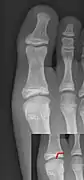

An X-ray of the left ankle showing a Salter–Harris type III fracture of medial malleolus. Black arrow demonstrates fracture line while the white arrow marks the growth plate.